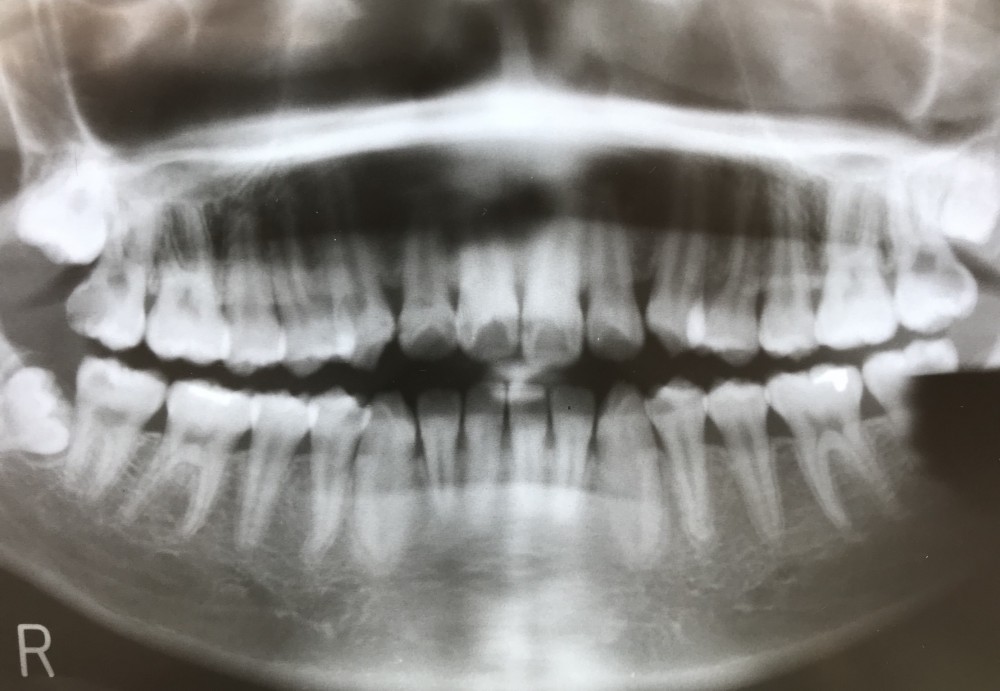

下の写真は、初診時、22才6ヶ月のものです。

上の画像で見ていただきたいのは、特に左上78です。

左上7も、初めは保存治療を開始しましたが、8の歯冠は近心方向に向いており、7抜歯後には8が代わりに7の位置に萌出すると予想されました。結局7は抜歯しています。